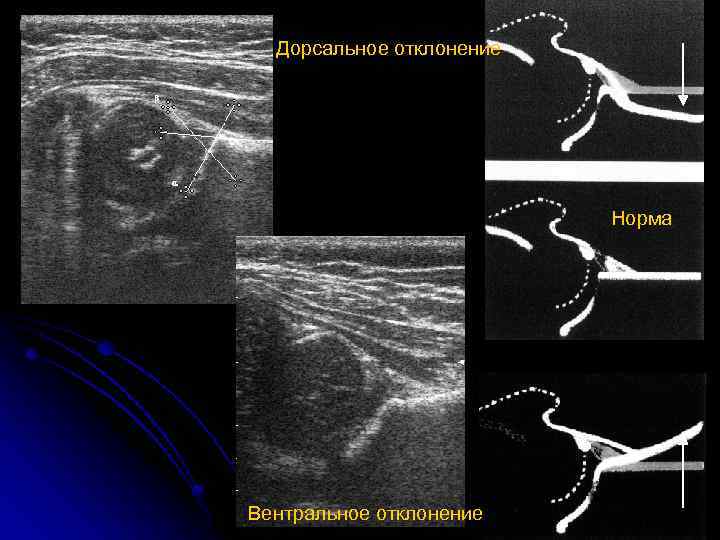

Дорсальное отклонение Норма Вентральное отклонение